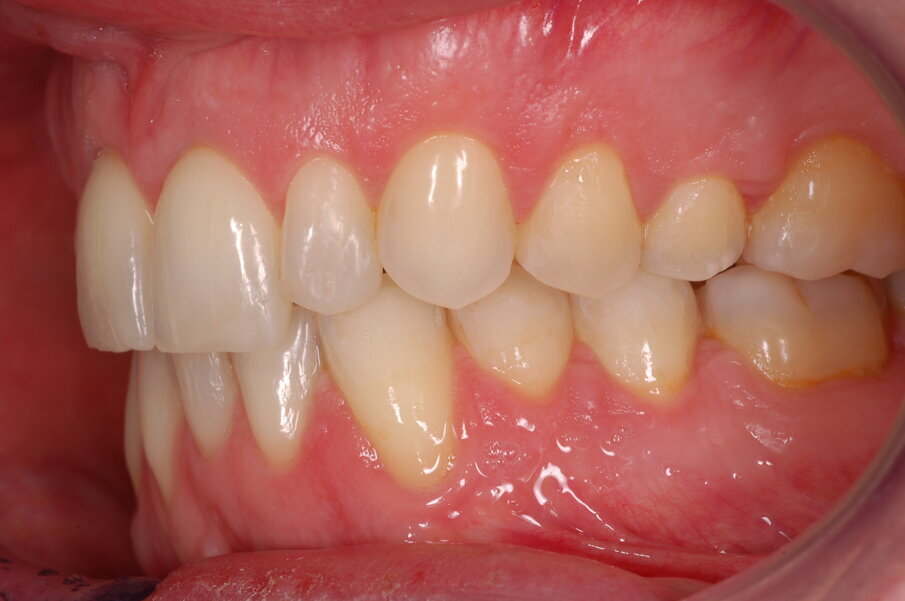

Diagnosi ed eziologia Un uomo sano di 39 anni si è presentato nel nostro studio ortodontico lamentando un aspetto dentale poco attraente e la paura della chirurgia ortognatica proposta da un altro ortodontista. Clinicamente, il profilo del paziente era rettilineo e la vista frontale non mostrava alcuna asimmetria facciale. L’esame funzionale non ha rivelato alcuna deviazione mandibolare o riduzione dei movimenti. Il paziente non aveva dolori articolari e non sono stati rilevati rumori articolari. Era presente una lieve occlusione molare bilaterale di Classe II, un morso aperto e un grave affollamento in entrambe le arcate. L’affollamento era particolarmente grave nell’arcata mandibolare, sebbene mancasse l’incisivo centrale mandibolare destro. Gli incisivi mascellari erano di piccole dimensioni, suggerendo una discrepanza dell’indice di Bolton se fossero stati presenti tutti e quattro gli incisivi mandibolari. Erano inoltre presenti un morso incrociato nella regione dell’incisivo laterale superiore sinistro e una grave rotazione distale del secondo premolare mandibolare sinistro (Figg. 1-8).

Figg. 1-8_Fotografie facciali e intraorali pre-trattamento.